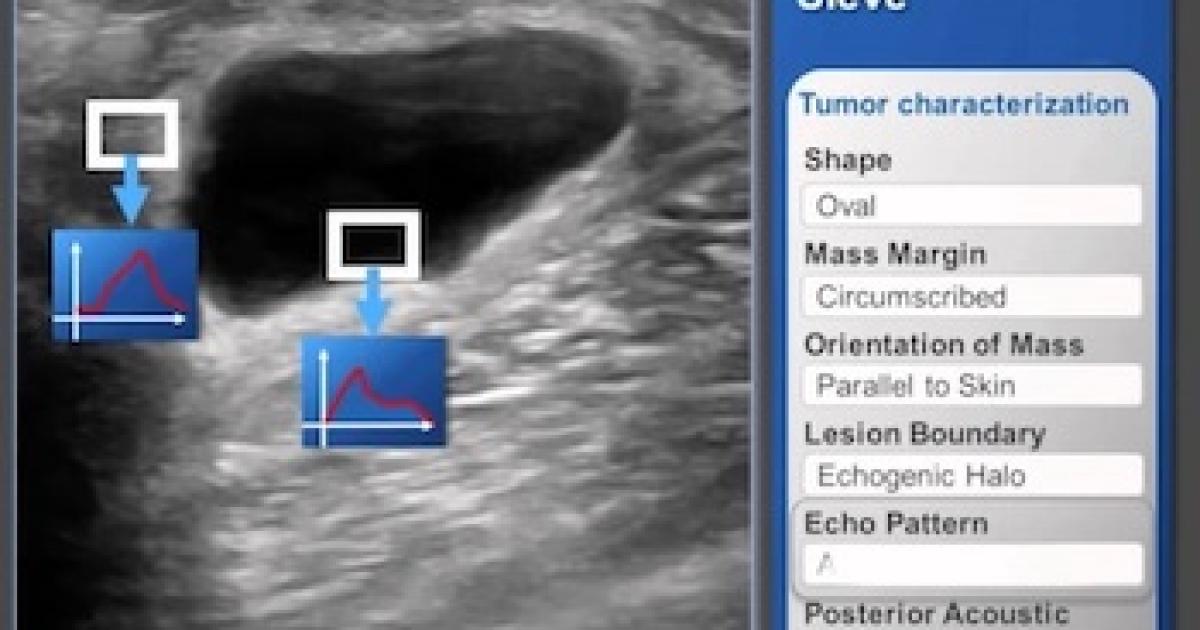

Interface of Medical Sieve, an algorithm by IBM for assisting in clinical decisions. (Image: The Medical Futurist – CC BY 4.0

Machine learning is now impacting healthcare, for example a computer analysing an MRI image and determining if you have cancer – assisting or potentially replacing a radiologist. "This is not science fiction," says Hansen. "Automatic diagnosis in medicine was already approved by the American Food and Drug Administration (FDA) in 2018."